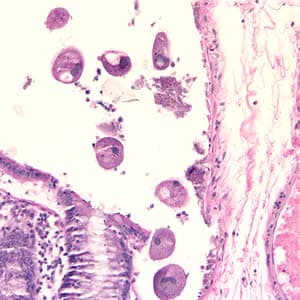

Balantidium coli cysts in wet mounts.

Both Balantidium coli trophozoites and cysts may be shed in stools. Both stages may occur in diarrheal stools, and usually only cysts are observed formed stools. Trophozoites are characterized by: their large size (40 µm to 200 µm), the presence of cilia on the cell surface, a cytostome, and a bean shaped macronucleus which is often visible and a smaller, less conspicuous micronucleus. Cysts are seen less frequently and range in size from 50 µm to 70 µm. B. coli trophozoites can also invade tissue.